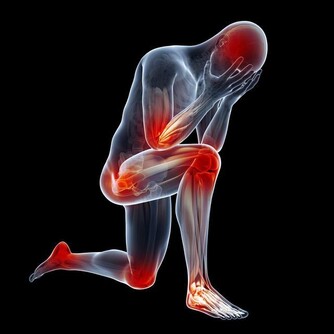

此種疾病多發於40歲以上人群,且女性病發率相對更高一點,而三叉神經痛屬於腦神經疾病,三叉神經痛之所以會引起牙痛,與三叉神經的分佈有很大關係。

它主要分佈於臉部,而三個點的其中兩個點,就是位於上頜和下頜,當三叉神經出現病變後,也就可能會觸發到上下頜,從而引發牙痛。

牙痛的現象,表現更為強烈,也是可能會受到上下頜活動的影響,比如說吃東西、打噴嚏、大笑、耳朵癢這些情況,都可能會讓牙痛的感覺更為強烈。

還需了解一點,就是三叉神經痛,發作的大多都比較突然,停止得也比較突然,而引起的疼痛感覺也是多樣化的,但大多都不能讓人忍受,即便只是持續很短時間,也會讓人忍受不住。

三叉神經痛,不是一個應該被忽視的疾病,40歲以後的人群,應該早做預防,畢竟,三叉神經痛發生後,帶來的痛苦也是很煎熬,不僅僅是引起牙痛,還可能出現臉痛、偏頭痛,被疼痛折磨的人,也是如坐針氈,希望你能引起重視。